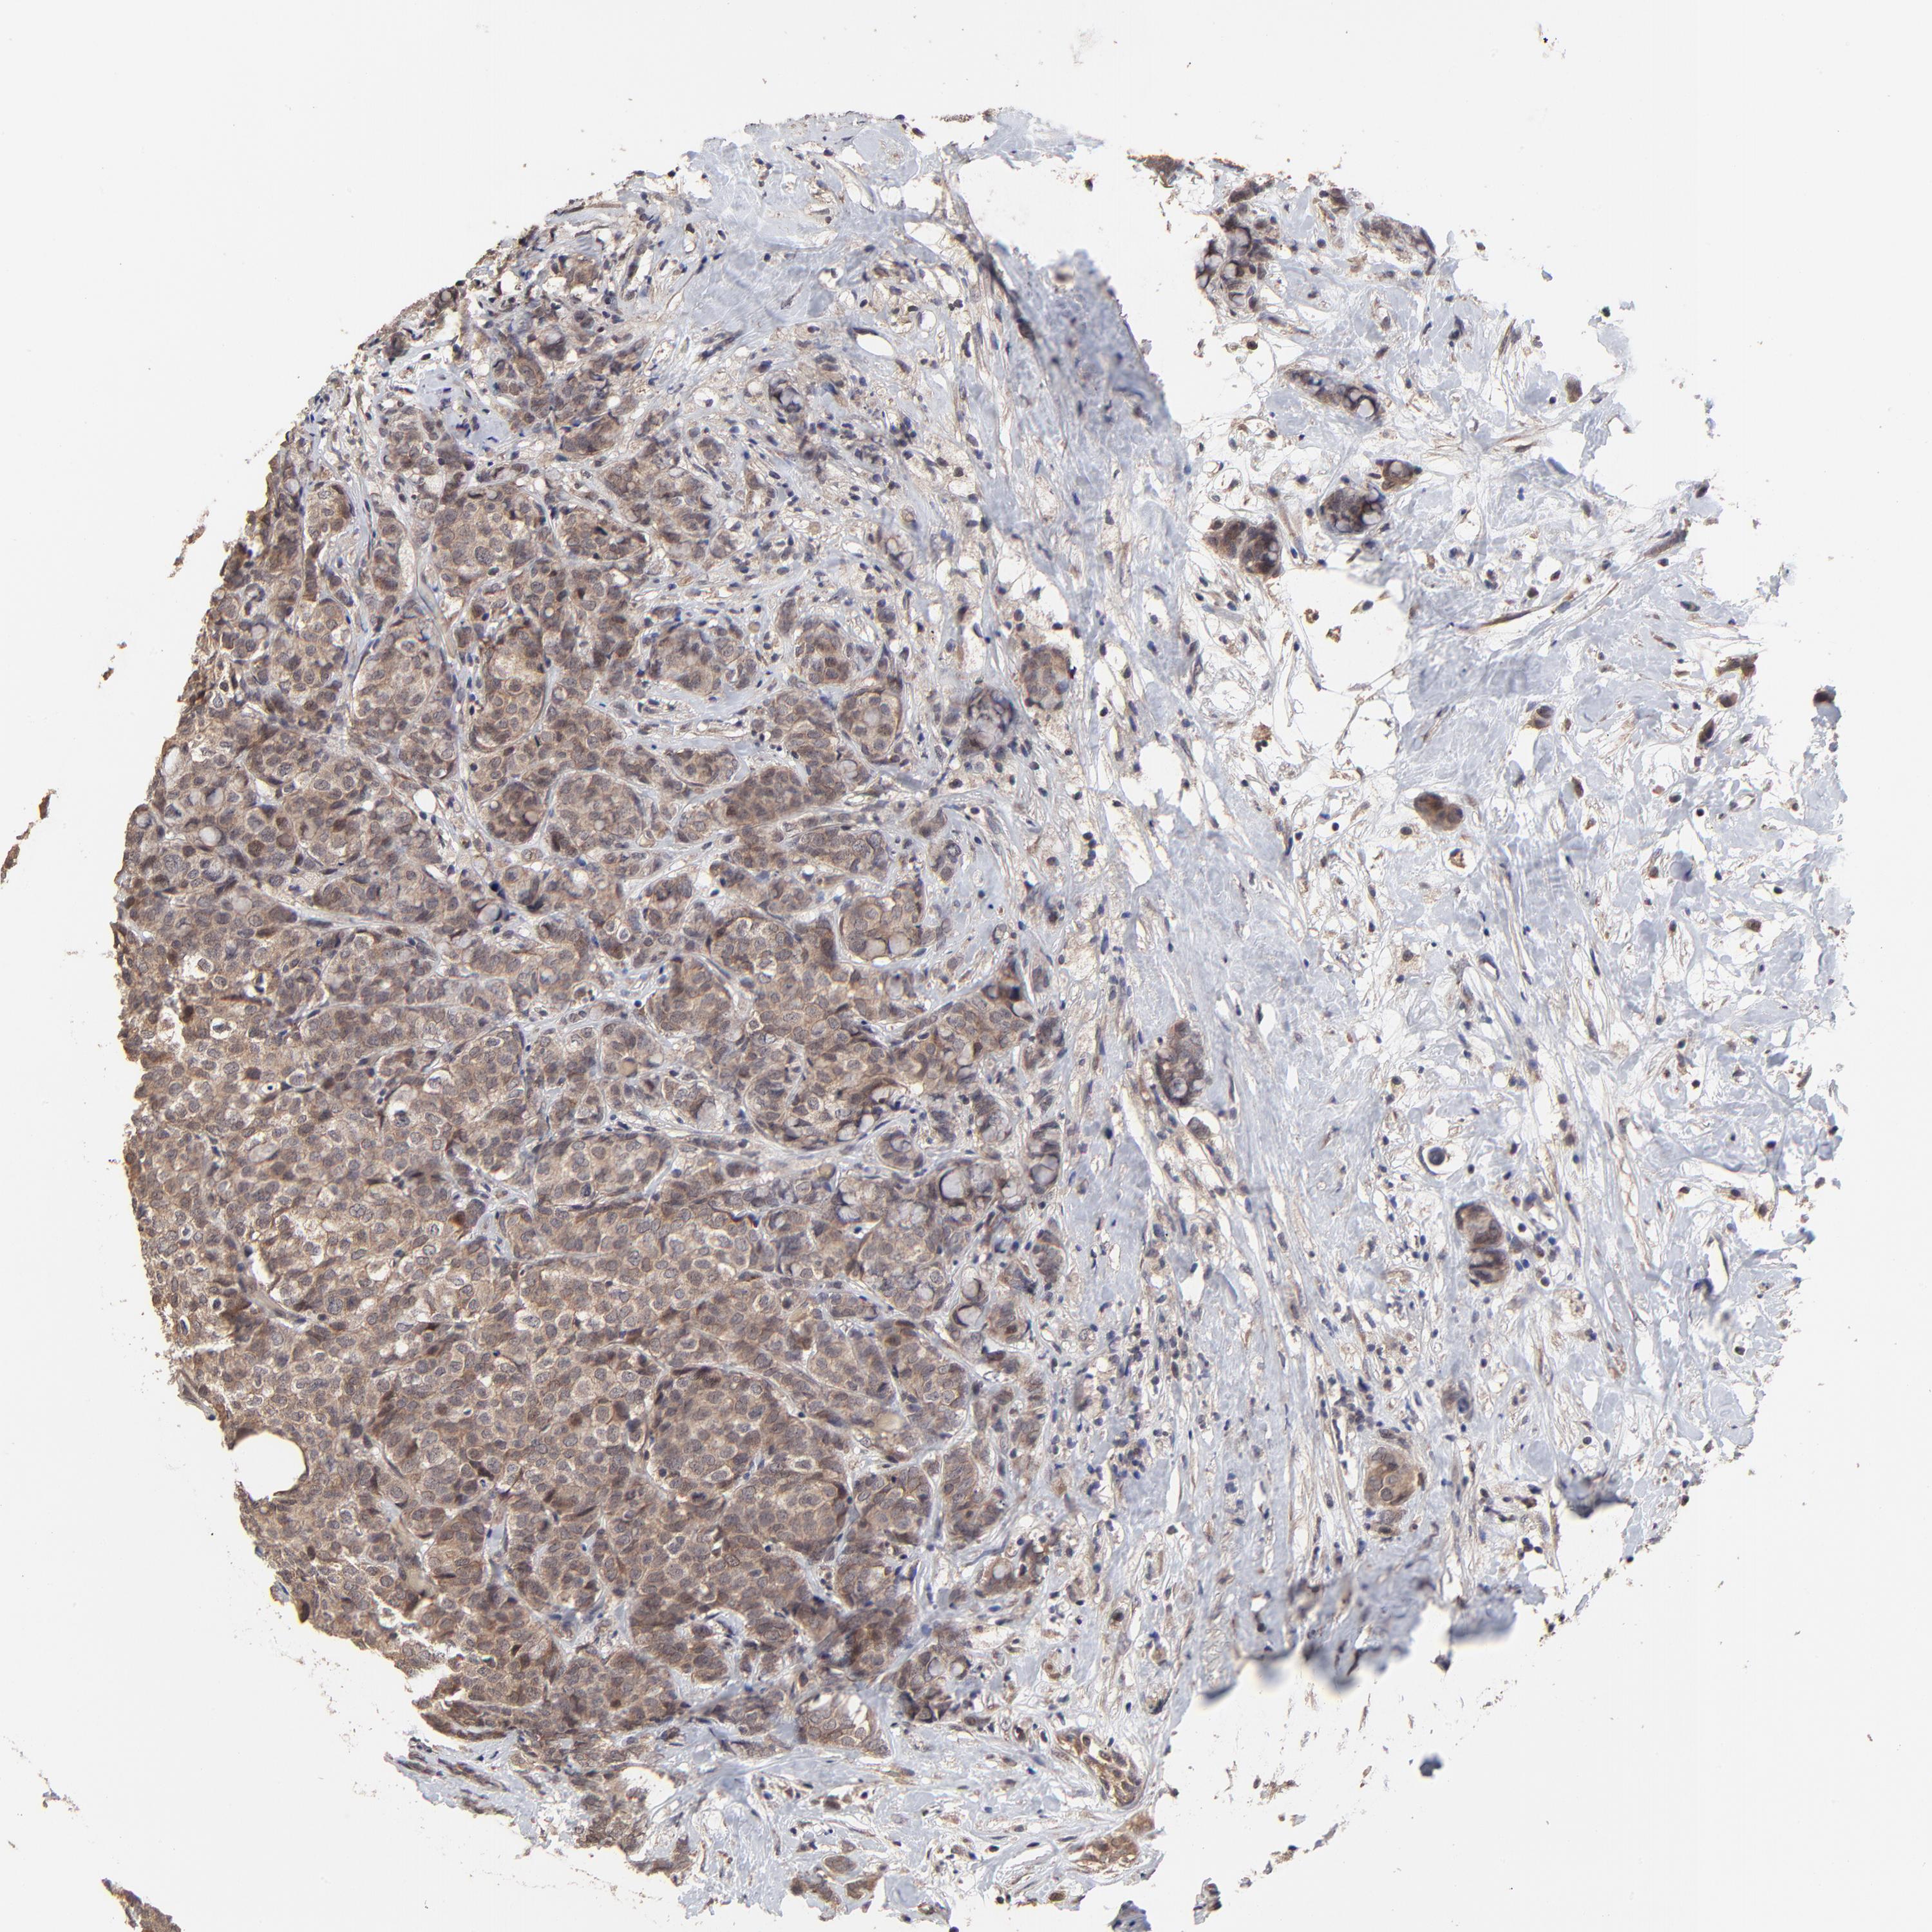

BRCA TCGA BRCA VALIDATION PROTEIN EXPRESSION